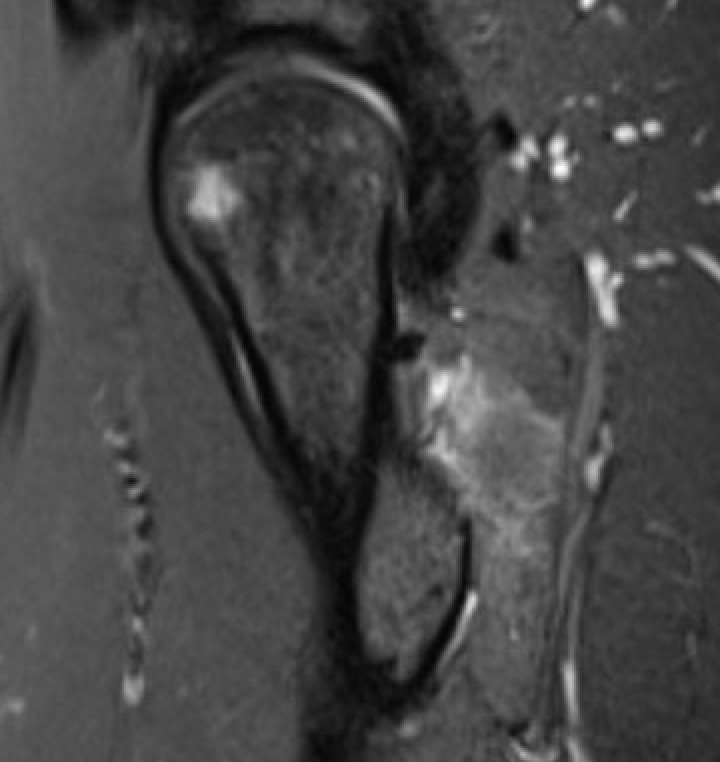

MRI

Reduced ischiofemoral space - distance between the lesser trochanter and the ischial tuberosity

Reduced quadratus femoris space - distance between hamstring tendon and iliopsoas

Inflammation / edema in quadratus femoris +/- fatty degeneration

Singer et al Skeletal Radiol 2015

- systematic review of 190 hip MRI of patients with ischiofemoral impingement

- compared to controls

- ischiofemoral space < 15 mm: sensitivity  77%, specificity 81%, accuracy 78%

- ischiofemoral space < 10 mm: sensitivity 79%, specificity 74%, accuracy 77%.